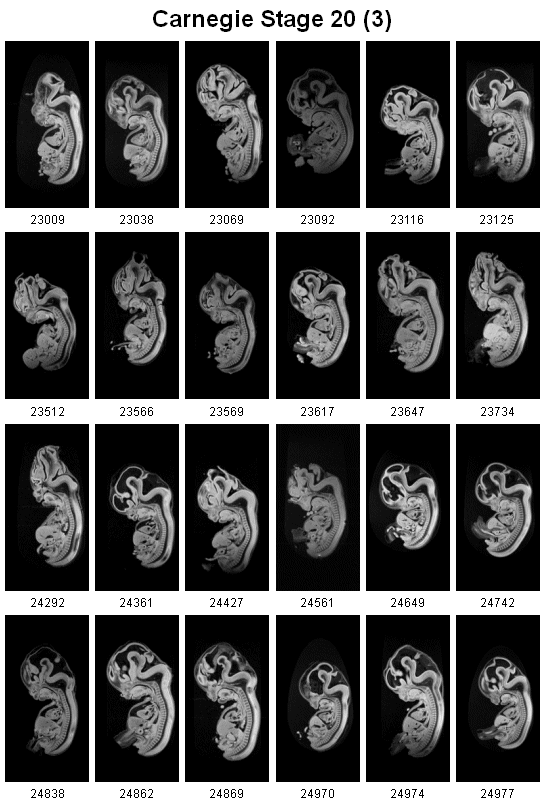

3rd page